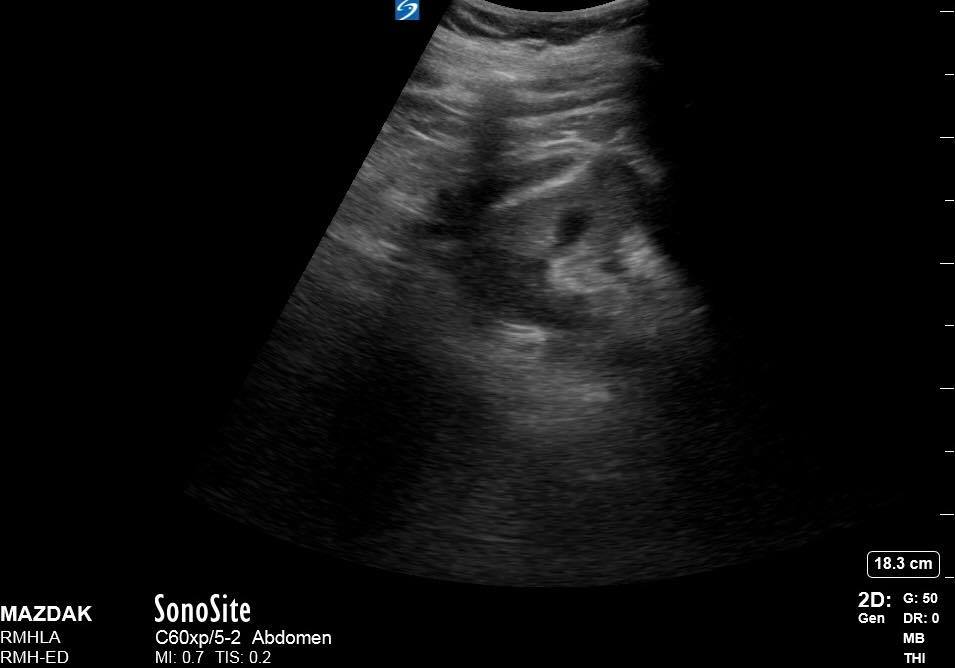

Maz saw a 65yo male in July with sudden onset. LLQ pain. Hx of HT and diverticulitis. BP101/80 HR 82.

Maz did a bedside US:

It showed a 8cm AAA

Perinephric FF on the left

Image 3: perinephric FF